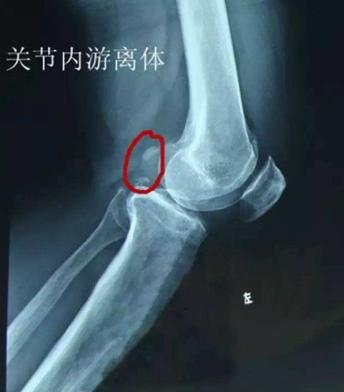

关节软骨无法在特定位置转变为骨骼,直接令到这区域的软骨增厚,增厚的软骨与周围正常的软骨分离形成了皮瓣,这一系列过程便称之为OCD。异常软骨的皮瓣有可能会发生从关节表面脱离,形成“关节鼠”。

图为“关节鼠”

那么,什么是“关节鼠”?

这一术语较好理解,意指关节出现病变的时候,在关节软骨内部会有自行脱离的“小碎片”。如前文提到,关节之间有“小碎片”的存在,容易发生疼痛等一系列影响。

兽医口中所说的“关节碎片”